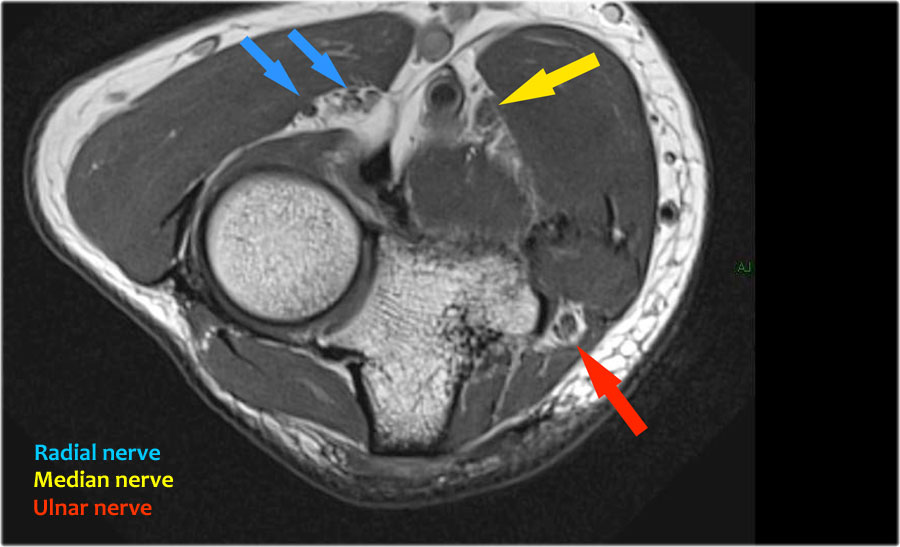

Dây thần kinh quay có thể được xác định rõ nhất ở mức chỏm xương quay, nơi có thể quan sát thấy các nhánh nông và nhánh sâu trong ống xương quay (mũi tên).

This is a very consistent place to find the radial nerve.